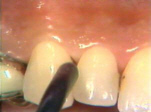

| El lado derecho presenta

la misma condición gingival que el izquierdo. |

Después de 2 meses del

tratamiento la gingiva es saludable y las profundidades de los

surcos (bolsas) periodontales están reducidas. No se observa

sangrado al sondaje. |

| Fotografía anterior al

tratamiento, que sirve como comparación. Hay abundante placa y bolsas

periodontales profundas. |